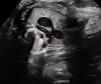

We present the case of a Saharawi pregnant woman with an unremarkable family and personal history. In the current pregnancy, there was evidence of intrauterine growth restriction (<3rd percentile) and fetal blood flow redistribution. The prenatal ultrasound conducted at 38+1 weeks detected an aneurysmal dilatation of the ductus arteriosus (Figs. 1 and 2), so the decision was made to induce labor and admit the infant to the neonatal unit for monitoring due to the potential complications associated with this condition (including spontaneous rupture, embolism, airway erosion, infection, compression of adjacent structures or even death).1,2

Prenatal ultrasound. 2D mode. Three-vessel and trachea view. The “V” shape produced by the aorta and pulmonary artery appears in the top left of the image. Visualization of the ductus arteriosus with a saccular dilatation with an aneurysmal appearance and a transverse diameter of 10 mm.

Structures: (1) pulmonary artery, (2) aorta, (3) superior vena cava, (4) ductus, (5) trachea.